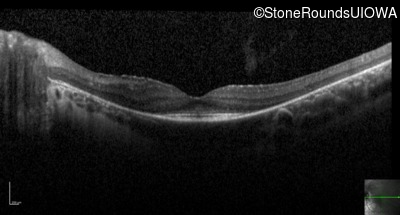

Optical Coherence Tomography - Right - 20/20 sc

Exemplar / OCT Stack

Optical Coherence Tomography - Left - 20/30 sc